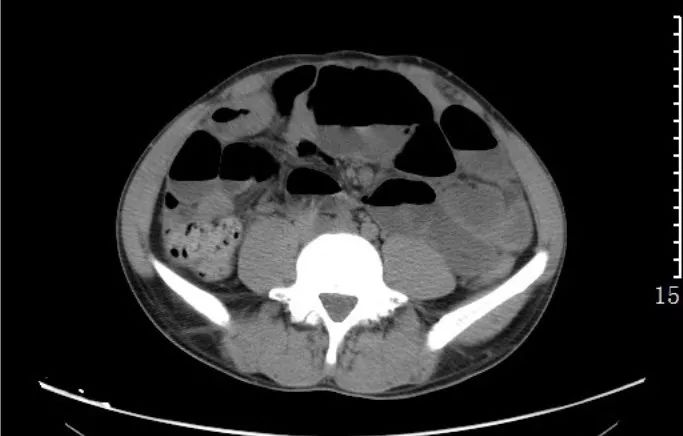

急性阑尾炎:CT平扫,阑尾增粗肿胀,腔内可见高密度粪石,阑尾浆膜面模糊,周围少许渗出。